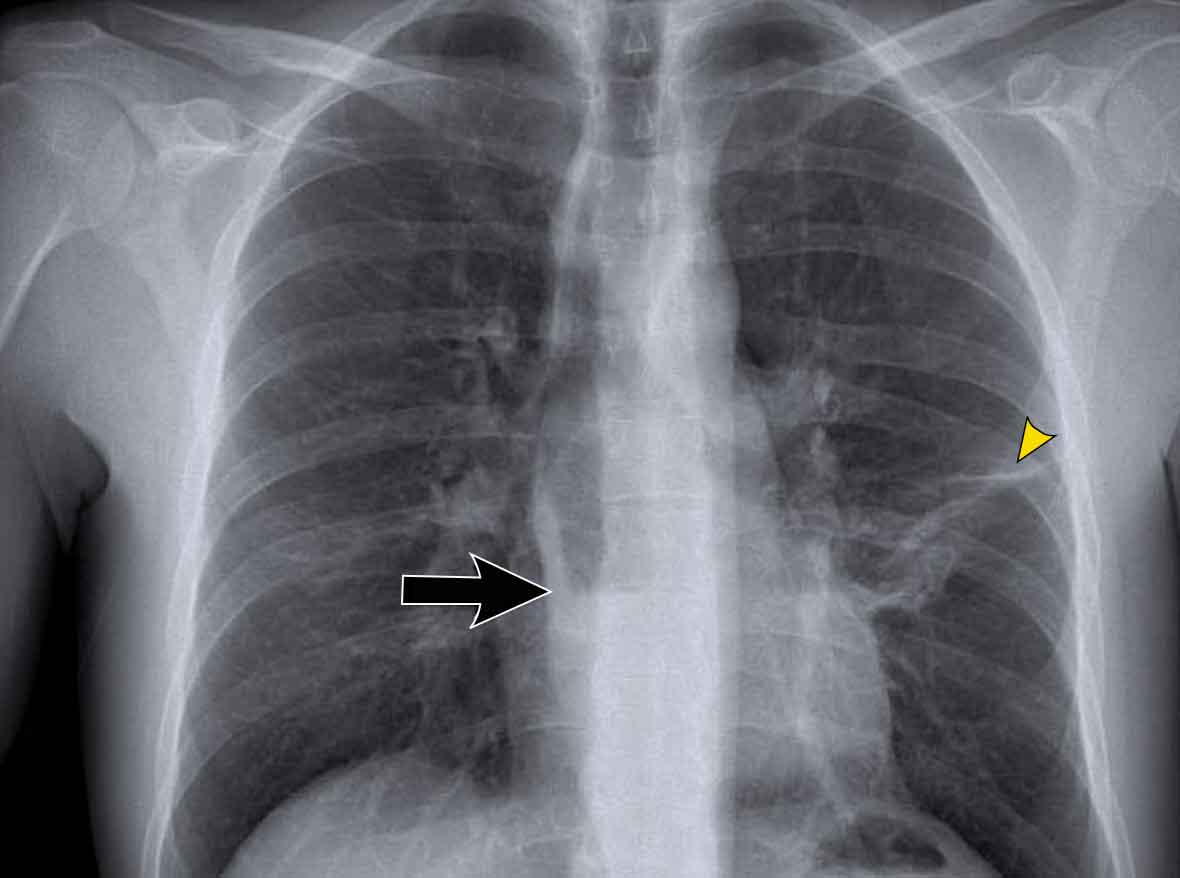

Case Example: Subtle Signs of Congestive Heart Failure

Begin by reviewing these current chest radiographs.

Based solely on these images, one might suspect congestive heart failure (CHF), though the findings are subtle.

Now review the previous study…

Scrolling between the current and prior films significantly increases diagnostic confidence in your diagnosis of congestive heart failure.

Key comparative findings include:

• Cardiac size: Slightly increased compared to the previous study; however, cardiomegaly was already present.

• Pulmonary vasculature: Mild vascular engorgement suggesting elevated pulmonary venous pressure.

• Interstitial markings: Subtle signs of interstitial edema .

• Pleural effusions: Bilateral small effusions, with subtle changes in the inferoposterior borders of the lower lobes, suggesting fluid accumulation.